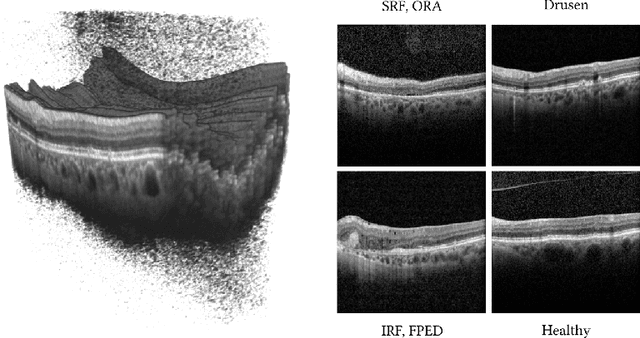

Abstract:Optical Coherence Tomography (OCT) is the primary imaging modality for detecting pathological biomarkers associated to retinal diseases such as Age-Related Macular Degeneration. In practice, clinical diagnosis and treatment strategies are closely linked to biomarkers visible in OCT volumes and the ability to identify these plays an important role in the development of ophthalmic pharmaceutical products. In this context, we present a method that automatically predicts the presence of biomarkers in OCT cross-sections by incorporating information from the entire volume. We do so by adding a bidirectional LSTM to fuse the outputs of a Convolutional Neural Network that predicts individual biomarkers. We thus avoid the need to use pixel-wise annotations to train our method, and instead provide fine-grained biomarker information regardless. On a dataset of 416 volumes, we show that our approach imposes coherence between biomarker predictions across volume slices and our predictions are superior to several existing approaches.